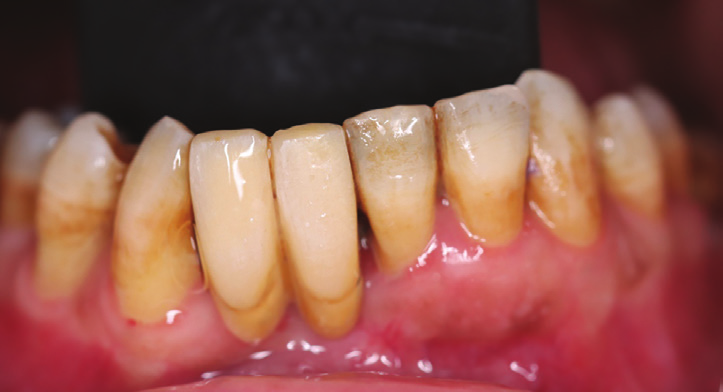

Figure 2: Intraoral view showing the extended bone and gingival loss with recession on both central incisor and canine.

Figure 3: Occlusal intraoral view showing the advanced amount of bone loss.

Intraoral examination showed a bridge replacing sites no 26 and 25 with a gingival extension replacing the bone loss in the area (Fig.1). Extra oral examination was normal.

After removal of the bridge an extended bone loss was found. (Fig.2, 3). X-rays and CAT views were taken for the region. The amount of bone loss was extended which was an indication for autologous bone graft. A PRF associated bovine bone technique was planned. A linear incision with mucoperiosteal flap elevation was conducted. The adjacent teeth showed also bone loss (Fig.4).